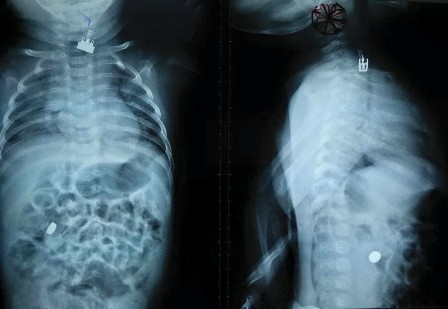

Hình ảnh X-quang ghi nhận chiếc công tắc đèn và cục pin trong cơ thể của trẻ

Tại đây, kết quả chẩn đoán hình ảnh bác sĩ ghi nhận, chiếc công tắc đèn đang đang kẹt trong thực quản bệnh nhi, riêng cục pin của thiết bị đồ chơi, đã rơi xuống đường ruột. Bệnh viện Nhi Đồng 2 tiến hành hội chẩn khẩn cấp, các bác sĩ thống nhất hội chẩn với chỉ định nội soi gắp dị vật cho bệnh nhi.